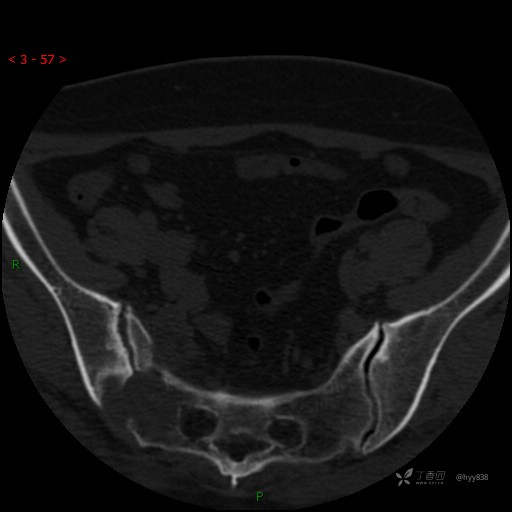

骶髂关节CT平扫